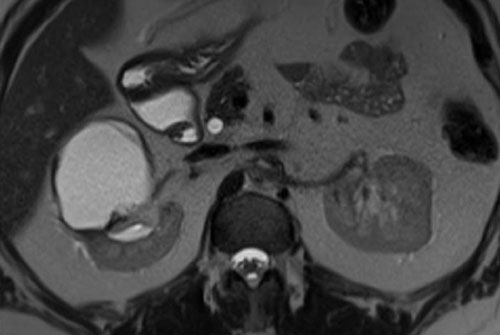

Có một khối dạng nang ở thận trái với nhiều vách ngăn mỏng ngấm thuốc.

Tổn thương được phân loại là Bosniak IIF.